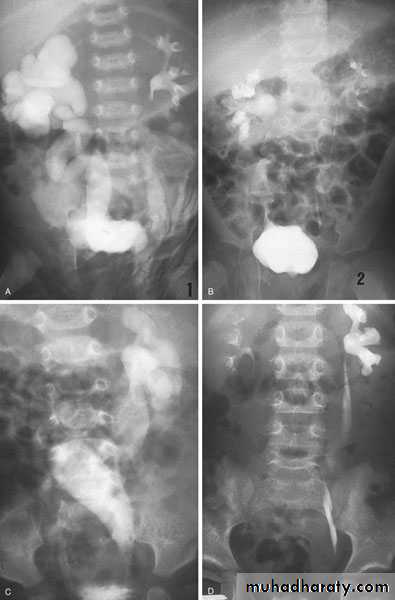

Found in 1:1000 necropsies and is more common in men.probably the most common of all renal fusion anomalies

The anomaly consists of two distinct renal masses lying vertically on either side of the midline and connected at their respective lower poles by a parenchymatous or fibrous isthmus that crosses the midplane of the body.

Fusion of the renal masses occurs early in embryonic life, so its ascent will be impeded by inferior mesenteric artery.

The kidneys are low located, mal rotated and pelves lie anteriorly

Diagnosis ultrasound, IVU, CT scan